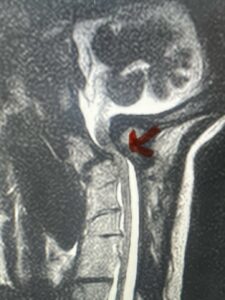

This is a 42 year-old female who presents with severe progressive weakness and numbness and difficulty with balance over a 6-month period. She has a history of having a motor vehicle accident at 5 years old but was never imaged. On exam she was noted to be severely myelopathic. Imaging revealed severe spinal cord compression at the level of C1 (Figs 4a and b).

Fig. 4a: Sagittal T2-weighted cervical MRI demonstrating severe cord compression with myelomalacia of upper cervical spinal cord (red arrow). Notice the increased atlanto-dens interval (red dot).

Fig. 4b: Axial T2-weighted cervical MRI demonstrating severe spinal cord compression from atlanto-axial instability (red arrow)

Cervical x-rays revealed a significantly increased atlanto-axial interval (Fig. 5) On review of her imaging studies it was noted that the right C2 isthmus was very thinned by the vertebral foramen (Figs 6a, b, and c) which would make an attempt at placing a C2 pars screw dangerous. A decision was made to perform an occipital-cervical fusion because only possible unilateral fixation and an extensive C1 laminectomy to be performed eliminating a fixation point if a more traditional C1-C2 was performed. Even if C1 lateral mass screws were able to be placed one could only perform a unilateral screw construct fixation to C2. We performed an occipital cervical fusion down to C4 to get enough inferior fixation and C1 laminectomy. The decompression went well. We placed a left unilateral pars screw and bilateral C3 and C4 lateral mass screws. We placed three 12 mm screws in the midline keel (Fig. 7). Postoperatively the patient had all around improvement in her symptoms and did not qualify for rehab. Her post op films at 6 weeks (Fig. 8)